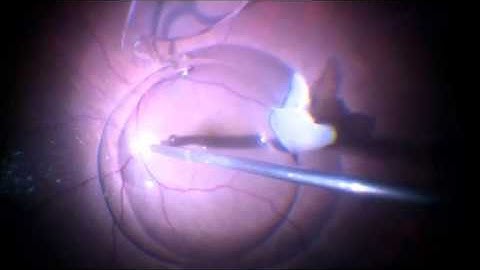

Management of a Dislocated IOL